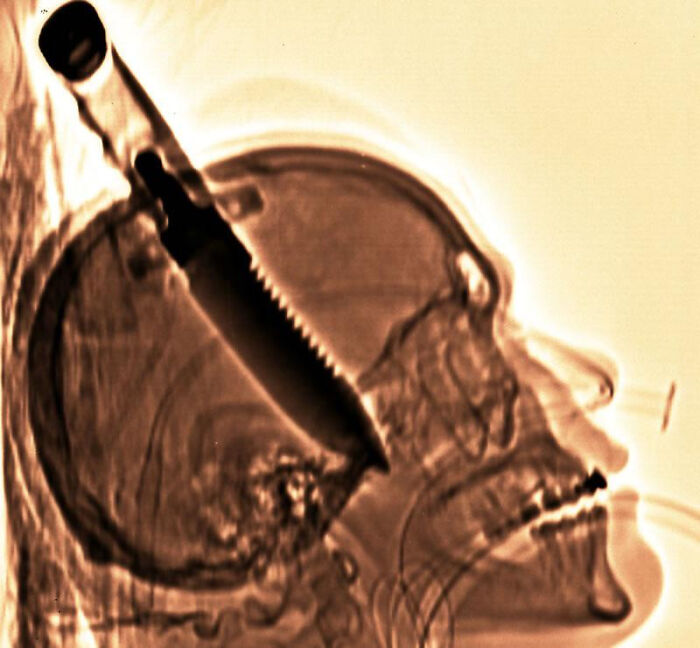

In 1998, Michael Hill Was Stabbed In The Brain With An 8-Inch Serrated Blade When Answering Door At Friend’s House.

"After 7 days, he left the hospital with memory loss & a paralyzed left hand. The knife caused permanent memory damage, but it was the largest object ever removed from a human brain."